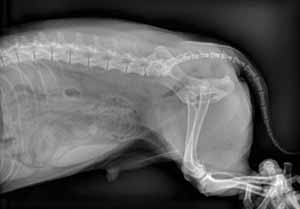

Abdominal radiographs:

Ventral deviation of colon consistent with sublumbar lymph node enlargement.